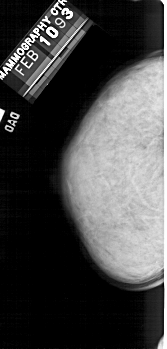

A_1342_1.RIGHT_MLO

RIGHT_MLO LINES 5416 PIXELS_PER_LINE 2671 BITS_PER_PIXEL 12 RESOLUTION 43.5 OVERLAY

FILE: A_1342_1.RIGHT_MLO.OVERLAY

TOTAL_ABNORMALITIES 1

ABNORMALITY 1

LESION_TYPE CALCIFICATION TYPE AMORPHOUS DISTRIBUTION SEGMENTAL

ASSESSMENT 4

SUBTLETY 3

PATHOLOGY BENIGN